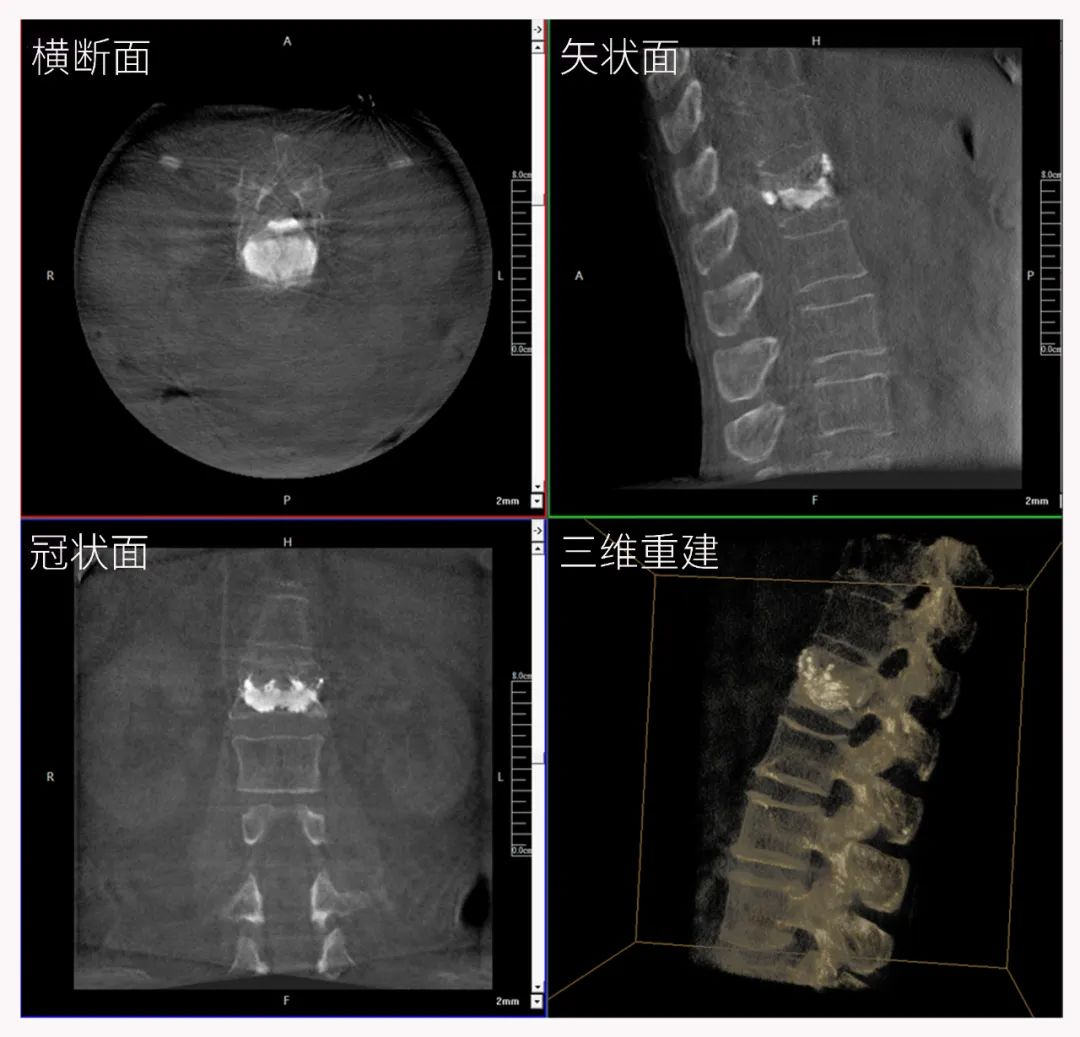

病例1:右側股骨遠端骨骺骨病(13歲)

二維影像看不到病灶點

三維切面影像可以看出病灶點